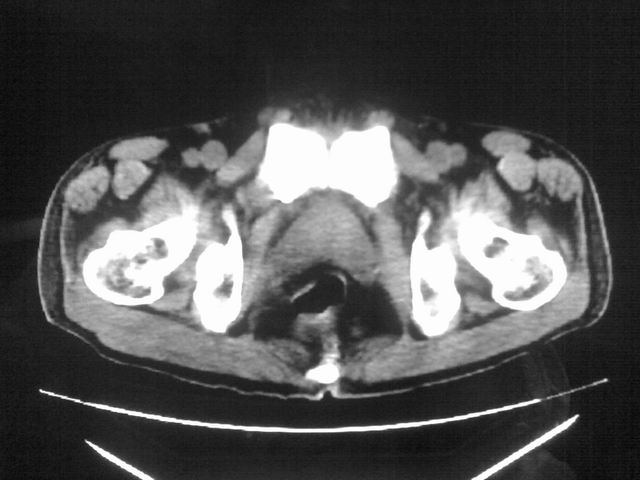

患者m 56岁,盆腔及下腹部胀痛半年,加重1月余,消瘦\中重度贫血.(附:平扫时直肠的高信号为,残留的钡剂).补一下病史:胃镜及纤维结肠镜均无明显异常.

前列腺癌或是精囊腺癌可能吗??

膀胱后方及直肠前方见巨大混杂密度影,与前列腺相连且向膀胱内突入,精囊腺显示不清;考虑前列腺癌侵犯精囊、膀胱。

膀胱及直肠间有不规侧的软组织密度影,内密度不均匀。其内有坏死囊变,前列腺及精囊腺,膀胱后壁受浸。结合病史考虑腹膜后肉瘤可能性大。